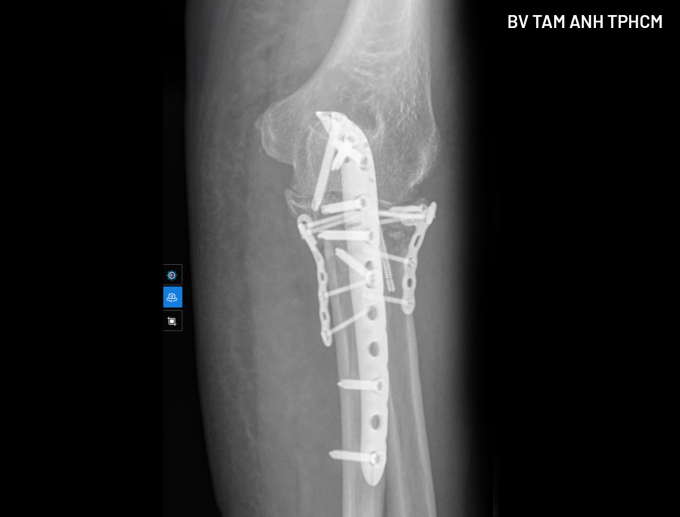

Để an toàn cho ca mổ, bác sĩ điều trị nội khoa cho bà Lợi trong 5 ngày, ổn định các chỉ số. Khi phẫu thuật, bác sĩ tiếp cận ổ gãy chỉ bằng một đường mổ duy nhất, từ phía sau, nắn chỉnh cả xương quay và xương trụ (mỏm khuỷu phía sau và mỏm vẹt phía trước) về đúng vị trí, sử dụng vít và nẹp để cố định, phục hồi giải phẫu hoàn toàn. Phương pháp này giúp giảm tối đa mất máu và tổn thương thần kinh mạch máu, các mô mềm khác. Người bệnh phục hồi nhanh hơn và giảm nguy cơ xảy ra biến chứng.

Kết quả chụp X-quang tay phải người bệnh sau phẫu thuật. Ảnh: Bệnh viện Đa khoa Tâm Anh